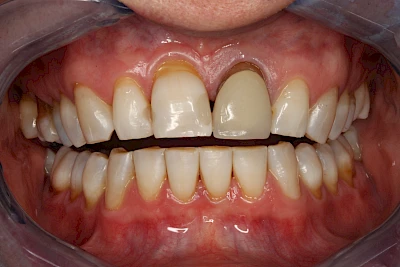

Verfärbungen an Zähnen können außen aufgelagert oder im Zahn eingelagert sein.

Von außen (exogen) eher dunkel gefärbt und meist mehrere Zähne betroffen:

- Genußmittel (Tee, Kaffee, Rauchen)

- Medikamente (z. B. Eisen)

Äußere Verfärbungen durch Genußmittel oder Medikamente (Eisen!) lassen sich meist nur durch den Zahnarzt z. B. mit einer professionellen Zahnreinigung entfernen.